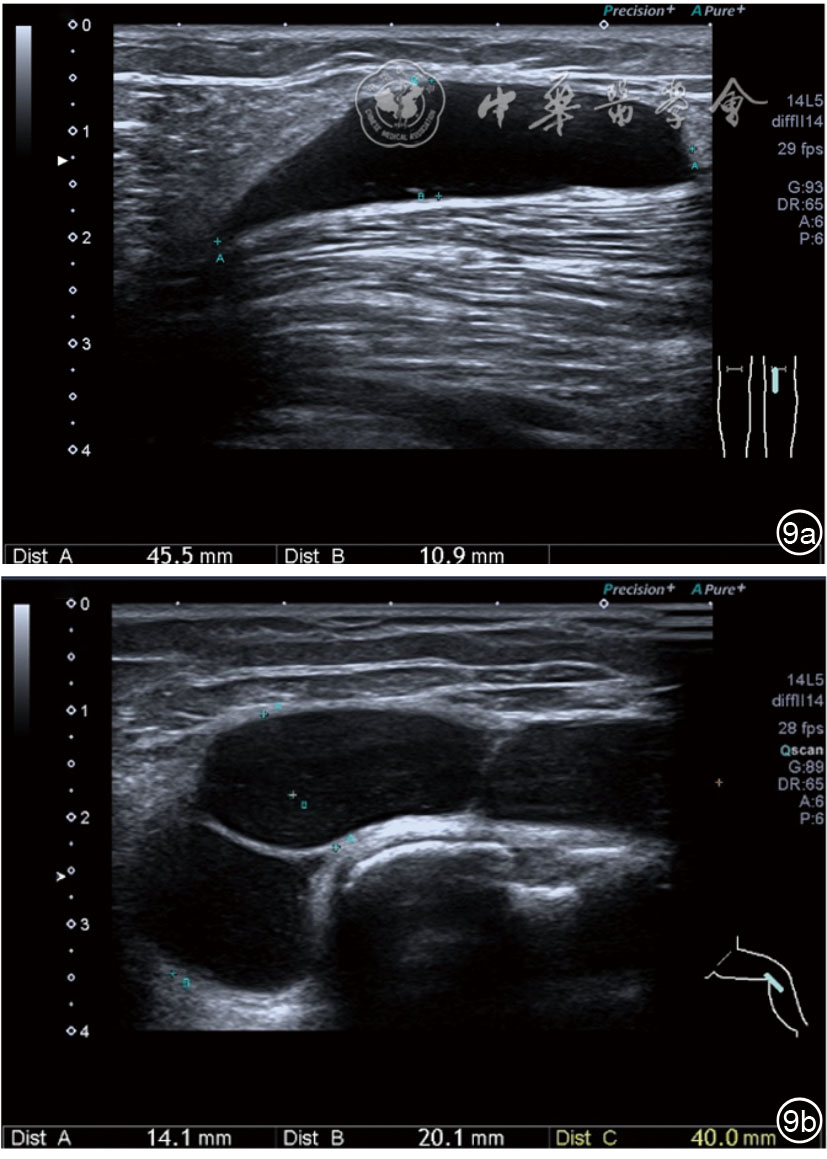

1.关节内表现。(1)骨改变。表现为骨末端或关节周缘出现的骨质局部突起改变,其后方伴或不伴有声影,多见于膝关节内侧缘和外侧缘(图1)。(2)软骨改变。股骨关节面改变可以在长轴及短轴切面显示,嘱患者屈曲膝关节,足平置于检查床,股骨滑车及股骨髁上半部分的关节面即可轻松显示。超声探查可见股骨负重面关节软骨发生不同程度的改变,轻者关节软骨浅侧边界模糊,重者可见关节软骨薄、缺失,软骨下骨缺损改变(图2)。(3)半月板外突。一般内侧半月板突出多见,外侧半月板突出比较少。半月板可见不同程度的外突,同时伴有膝内侧副韧带向外移位(图3)。半月板外周缘性滑脱是指半月板突出超出胫骨平台边缘的距离≥3 mm,其可引起一系列临床症状,早期诊断、早期治疗可以预防骨关节的进一步损伤。(4)交叉韧带损伤。可见前后交叉韧带增粗,回声减低(图4)。(5)髌上囊积液。膝关节是最容易发生积液的关节之一。患者仰卧位,关节积液最常见于膝关节上外侧,因为关节囊向髌股关节上外侧突出。髌上囊积液采用10~18 MHz的高频线阵探头于股四头肌腱纵断面及横断面扫查均可显示,探头频率取决于患者体型。超声可见低回声积液,慢性可伴有丛状滑膜增生(图5)。(6)脂肪垫水肿。脂肪垫在髌骨附着点处回声增强、增厚(图6)。

图1 关节间隙周边及关节骨赘形成超声图像

3.超声半定量评估。(1)骨赘超声半定量评估:患者仰卧位,膝关节伸直,探头纵切面置于膝关节内侧与外侧,自前向后移动探头以进行全面扫查。测量骨赘的厚度,并进行半定量分析。0级:无骨赘;1级:小骨赘,厚度<2 mm;2级:中等骨赘,厚度2.1~4.0 mm;3级:大骨赘,厚度>4.0 mm。(2)关节软骨超声半定量评估:患者仰卧位,膝关节完全屈曲。探头置于骨上方,检查股骨内侧髁、外侧髁和股骨滑车处关节软骨三个部位,分别进行横切面和纵切面检查,从近侧向远侧做全面扫查。检查时声束要垂直于股骨表面。关节软骨可按病变严重程度分为四级。0级:关节软骨呈均匀的无回声带,其浅侧和深侧边界清晰。1级:关节软骨浅侧边界不清和(或)内部回声增高。2级:①2A级,关节软骨局部变薄,缺损厚度<50%;②2B级,关节软骨局部变薄,缺损厚度>50%,但<100%。3级:关节软骨局部完全消失,伴或不伴有软骨下骨病变。(3)半月板突出分度:半月板外周缘与胫骨平台边缘之间的距离≥3 mm的突出视为病理变化,诊断为半月板周缘滑脱。按照突出程度分为三度:Ⅰ度,半月板外周缘与胫骨平台边缘之间的距离3~5 mm;Ⅱ度,半月板外周缘与胫骨平台边缘之间的距离>5~8 mm;Ⅲ度,半月板外周缘与胫骨平台边缘之间的距离8 mm以上。